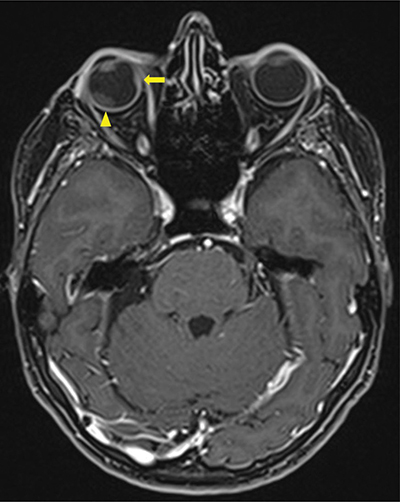

Figure 2

Contrast enhanced Axial T1 Dixon MRI-scan showing a second intra-orbital metastasis (arrow) invading all layers of the eyeball including sclera and a secondary retinal detachment (arrowhead).